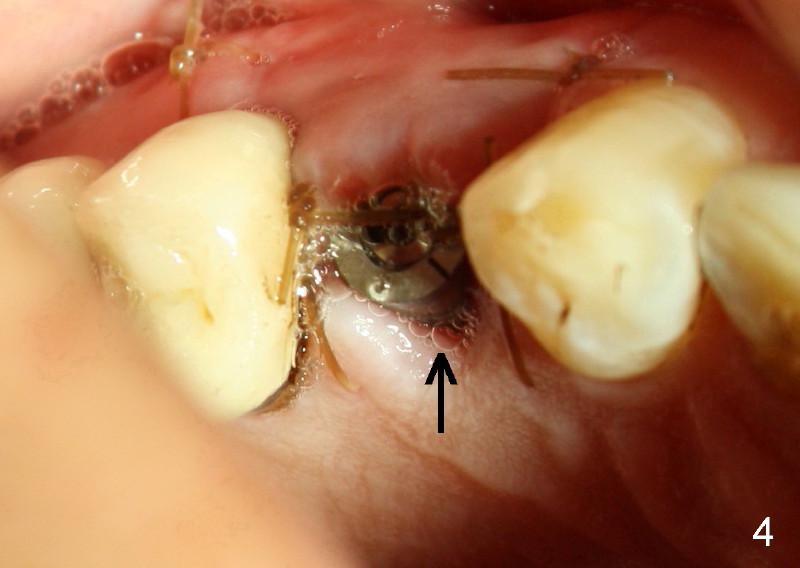

Sixty-eight year old healthy man has had multiple implants.  He readily accepted immediate implant when the tooth #5 had subgingival fracture of the lingual cusp (Fig.1).  A 5x20 mm Tatum screw implant was placed immediately after atraumatic extraction and bone expansion (Fig.2 I).  Implant rough surface was exposed buccally and lingually when the implant was placed equigingivally proximally.  Two buccal accessory incisions were made.  The flap was raised with scoring the periosteum underneath, advanced downward (as shown in Fig.3 arrow) and sutured to the lingual papilla.  The buccal aspect of the implant is covered, whereas the lingual rough surface remains partially exposed (Fig.4 arrow), assuming that the palatal mucoperiosteum is tough to advance even with release incisions.

Fig.3 and 4 are taken 1 week postop, whereas Fig.5 and 6 (mirror view) are taken 2 weeks postop.